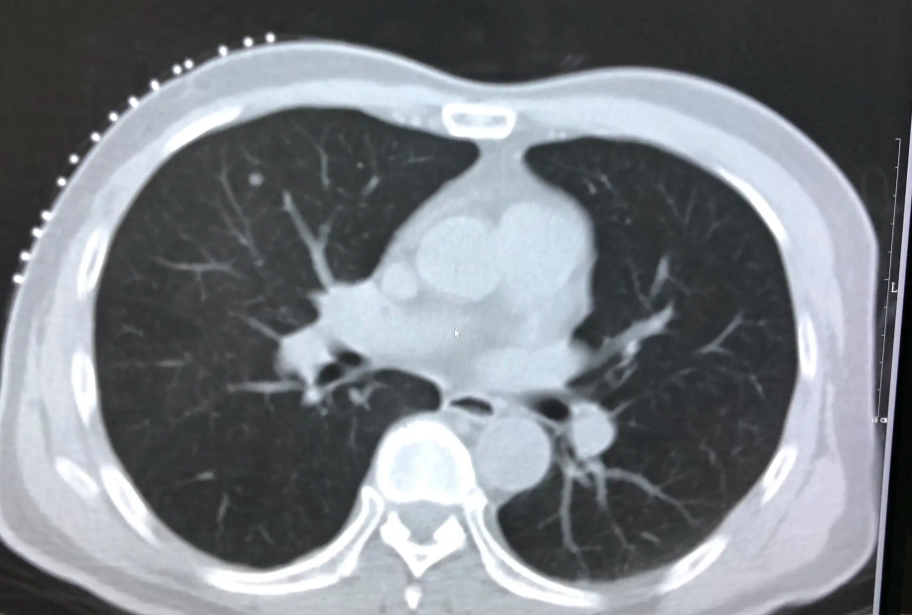

肺结节有三种类型:第一种是一个小于1厘米的小结节,称为肺部小结节;第二个是2-3cm的肺结节;第三种是1厘米以下的小肺节、3厘米以下的肺结节和3厘米以上的肺肿物或肺肿瘤。

然而,肺结节、肺小结节和肺肿物与恶性肿瘤不同,肺小结节与肺部恶性肿瘤不同。肺部有多发小结节意味着肺部有多个结节,但并非所有这些结节都是相同的。

有些是需要手术治疗的肺癌,有些不是肺癌需要密切观察,有些是可以通过抗炎剂解决的炎症,还有一些是出血、钙化灶等综合病症。因此,根据小结节的不同性质,采用适当的治疗方法,最好及时到正规医院的专科医生处进行早期诊断,然后及时进行有针对性的治疗。